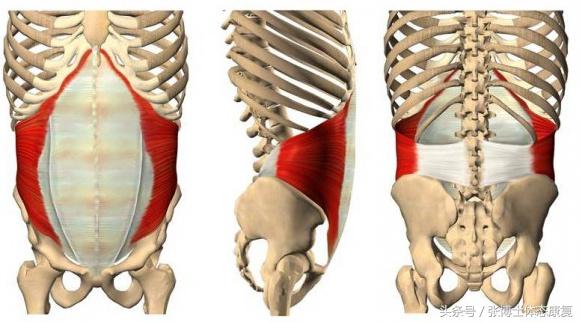

腹横肌训练

腹横肌位于腹部深层,收缩可以提升腹压,稳定骨盆,能够像个束带一样把骨盆从腰部一圈包裹住,腹横肌力量增强,有助于合并耻骨联合。